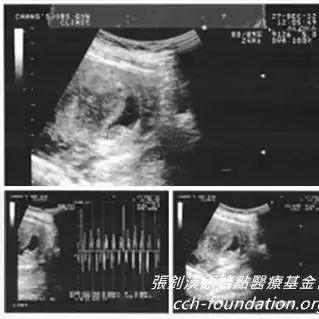

學員原始點應用與處理過程: 我是原始點臺北志工 2014年2月間一個晚上 上完廁所發現自己血尿了 當下就用兩斤多的生姜切片 用1000c.c.的水 熬煮成300c.c.的濃姜湯 喝完不久就不再血尿了 第二天起床 小腹部很不舒服 有時劇痛 有時陣痛 劇痛時手腳都是冰冷的 就這樣來來回回十多分鐘 之后就不再痛了 所以我也不在意 過了...